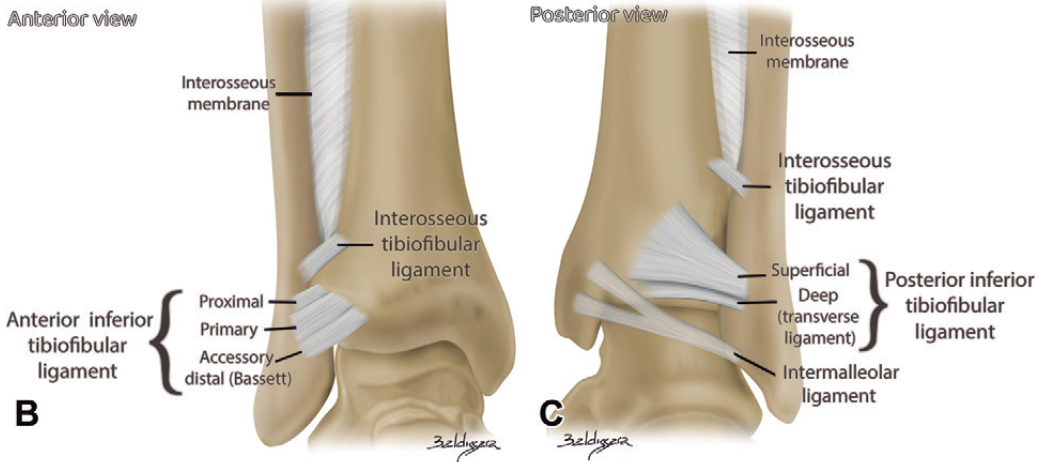

下胫腓前韧带

下胫腓后韧带

下胫腓后韧带由浅部和深部两个独立成分构成,通常所说的下胫腓后韧带指浅部成分,深部成分则被称为横韧带。该韧带整体近乎水平走行,与水平面成约20°角。其在腓骨侧的宽大止点可限制足部相对于小腿的过度外旋,以及腓骨远端相对于胫骨的过度活动。

浅部成分起自外踝后缘,向近侧和内侧走行,止于胫骨后结节;深部成分(横韧带)起自踝窝近侧区,通常止于胫骨远端腓切迹的后下角,部分病例中可延伸至内踝窝。深部成分的远侧纤维紧邻横韧带,部分腓骨侧止点纤维与横韧带相延续,因此难以区分其与邻近韧带的上下边界。从功能上看,该成分类似胫骨关节面后缘的盂唇样延伸结构,有助于维持关节稳定性,阻止距骨向后移位。

踝间韧带

胫腓骨间韧带